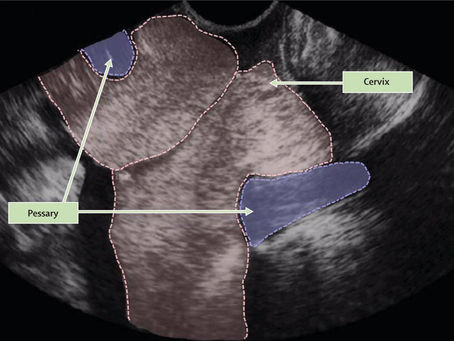

O que é Pessário Cervical?

Ter um bebê prematuro é um temor de muitas grávidas. A gravidez múltipla e a incompetência do colo são fatores de risco comuns para que...